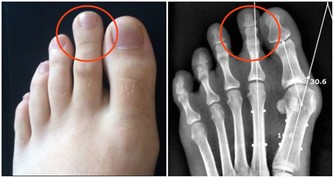

降壓第一招:控制鈉鹽攝入 每天不宜超過6克 鈉:高血壓的「搗亂分子」 北京大學第一醫院心內科主任霍勇教授表示,高血壓患者要做到飲食健康,首當其衝的就是控制鹽的攝入。鹽的攝入量降下來,降壓便可立竿見影。 平時總強調的限鹽,其實主要指的是降低鈉的攝入,因為食鹽的化學成分是氯化鈉,而鈉才是引起血壓升高的「搗亂分子」。 進食含鈉較高的食物,會引起水分在體內滯留,同時使血容量增加,鈉在體內蓄積還可引起小動脈收縮,導致心臟將血液注入血管的阻力變大,從而引發高血壓。

高血壓限制鈉鹽,刻不容緩! 我國居民膳食指南推薦一個人一天鹽的攝入量是6克,其中有2克鹽是人們日常吃進去的食物所包含的鹽量,實際一天炒菜用鹽量應是4克,4克鹽相當於把一個普通啤酒瓶蓋鋪平的量。 北京協和醫院營養科主任醫師於康表示,糖尿病或高血壓患者每天鹽的總攝入量不宜超過3克,高血壓、糖尿病並存的患者及腎臟疾病患者每天鹽的攝入量不要超過2克。